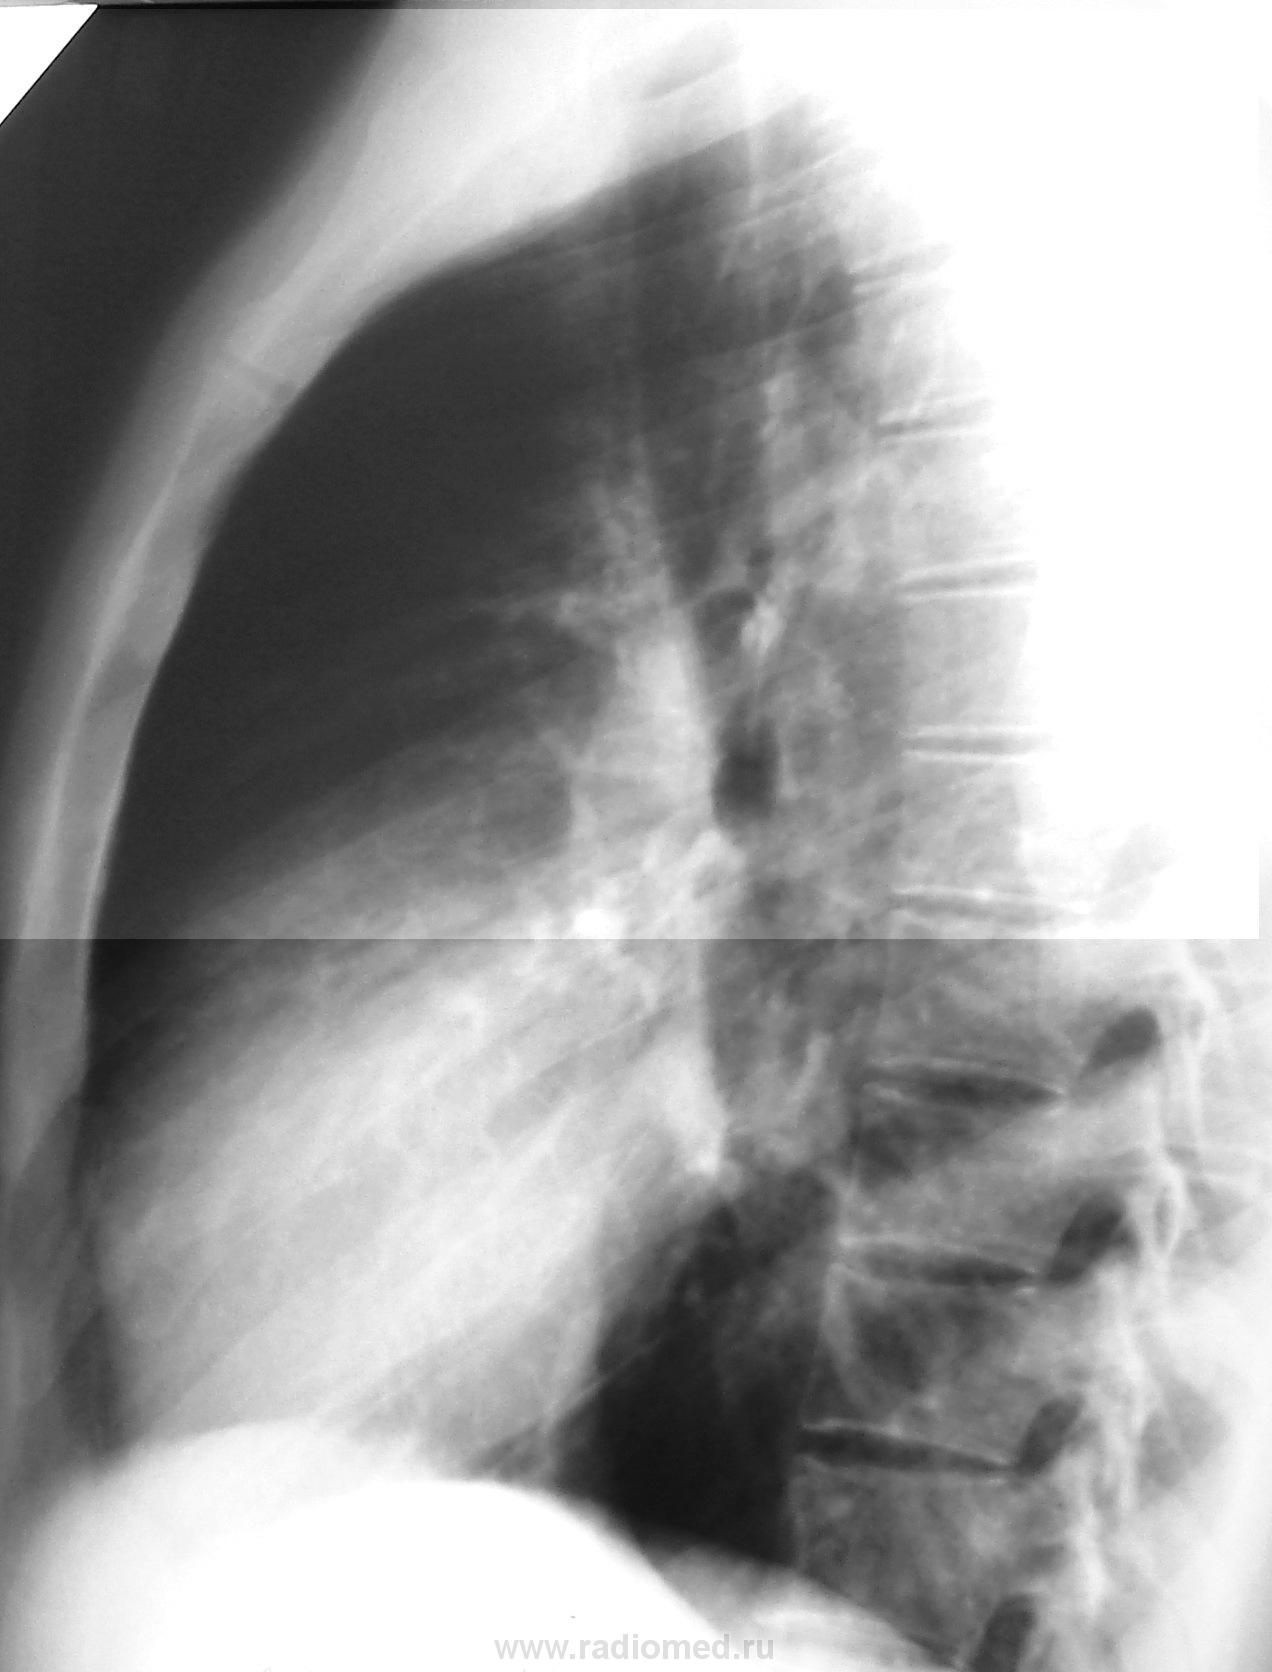

Я с Вами, Валентин Львович, если Вы туберкулез так называете. И вот почему: 1. море внутридольковых очажков с обеих сторон сверху донизу, 2. наличие крупного фокуса (хотя, и нетипично расположенного в S3). Т.о., получается туберкулез легких в фазе инфильтрации, распада и обсеменения. Распад поставлен не потому, что явно вижу полость (для этого надо смотреть дайкомы, в том числе и совсем тонкие), а потому что явное обсеменение - внутридольковые очажки..

При получении данных рентгенографии высказано мнение о наличии у больного пневмонии в S 3 левого легкого. Вместе с тем, при повторном посещении общее состояние этого молодого человека удовлетворительное: он бодр, нет потливости, аппетит превосходный, температура на приеме 36,4С, гемограмма оказалась нормальной. Клиническая картина не указывала врачу на пневмонию и у него возникла мысль о другом заболевании (туберкулёз?). Однако смущала локализация процесса (S3), которая не типична для специфического процесса. Учитывая ограниченный процесс, удовлетворительное состояние больного врач не бросился сломя голову назначать антибиотики по принципу, «полечим 2 недели, потом контроль и определимся», а назначил углубленное обследование (РКТ ОГК). Представляю Вам результаты РКТ. Других материалов нет. Дайкома нет. Ваше мнение после данных КТ .

По данным КТ-изображениям диф. диагностика между сосудистой мальформацией, БАР (пневмониеподобная форма) и шаровидной пневмонией.

Подождём других мнений. КТшников предостаточно, рентгенологов - тоже. Мне качество снимков с пленки не позволяет делать какие-то выводы, потому что по сагиттальной реконструкции диссеминация и образование с лучистостью, по аксиалам ничего подобного нет. Если поиграть резкостью и контрастностью, можно из очага сделать тень плотностью сходной с сосудом... В-общем, выбирать картинку для печати на плёнку можно по-разному, вот я о чём. Что хотел показать врач КТ или лаборант - я не знаю. Показано образование из извитых элементов, по цвету (плотность - ?) равных сосудам.